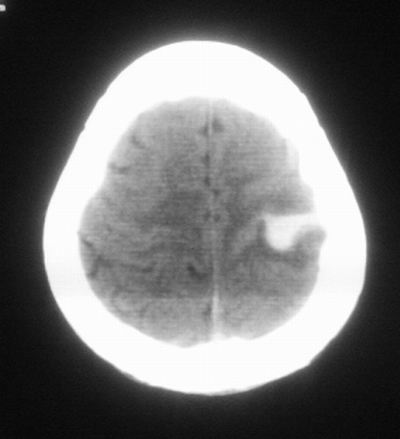

治疗三天后复查ct片示:

治疗三天后复查ct:除左侧额顶叶血肿外。左侧额叶另见片状低密度灶,密度不均匀,境界不清;考虑脑梗塞。

左侧额顶叶血肿伴出血后梗塞!